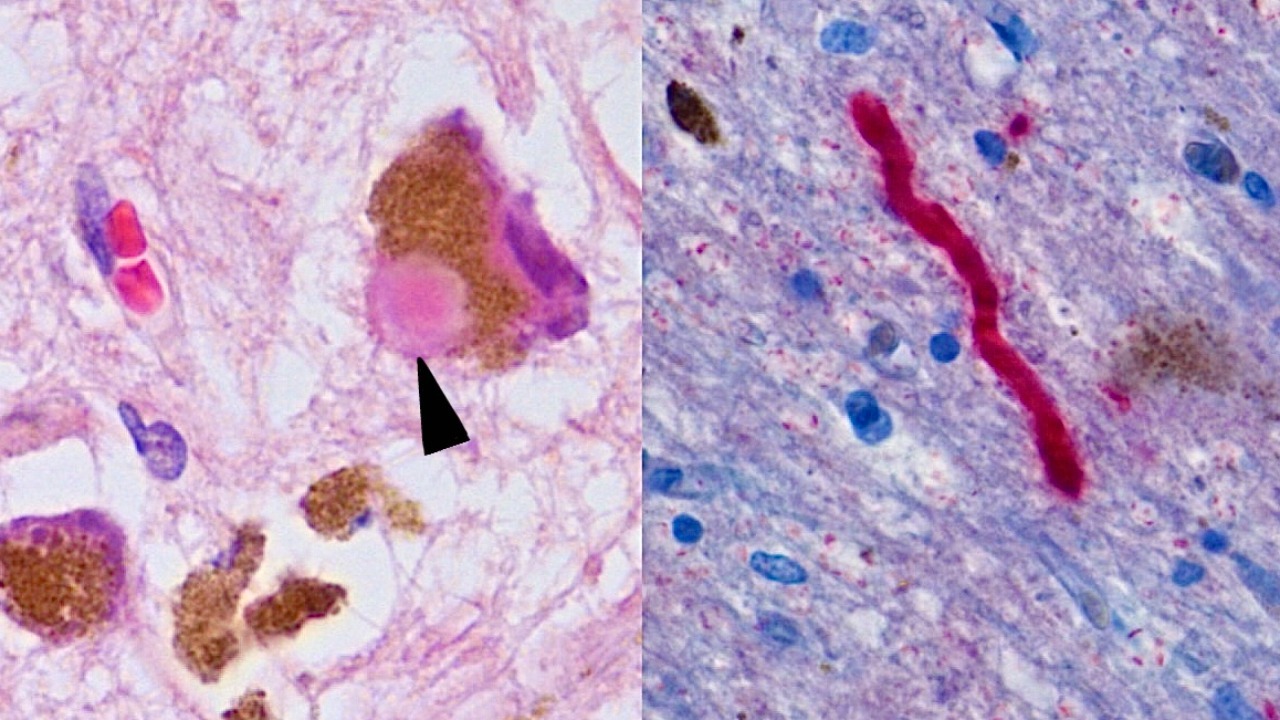

The study findings from Wuhan University present a fascinating new perspective on the origins of Parkinson’s disease. Using a combination of epidemiological studies and laboratory experiments, the researchers have found evidence suggesting that kidney dysfunction may precede the onset of Parkinson’s symptoms. This challenges the long-standing belief that the disease starts in the brain, suggesting instead that it might begin with renal complications. The study employed advanced imaging techniques and biochemical assays to track changes in kidney function and correlate these with early signs of Parkinson’s.

Biologically, the mechanisms by which kidney dysfunction could contribute to Parkinson’s are still being explored. One hypothesis is that impaired kidney function leads to the accumulation of toxins in the blood, which can then affect other organs, including the brain. This is known as the “gut-brain-kidney axis,” where each organ system can influence the others. The kidneys play a crucial role in filtering waste from the blood, and their dysfunction could lead to an increased burden of toxic metabolites, which might contribute to neurodegeneration. This new understanding could significantly impact the way we diagnose Parkinson’s, allowing for earlier detection through renal biomarkers.